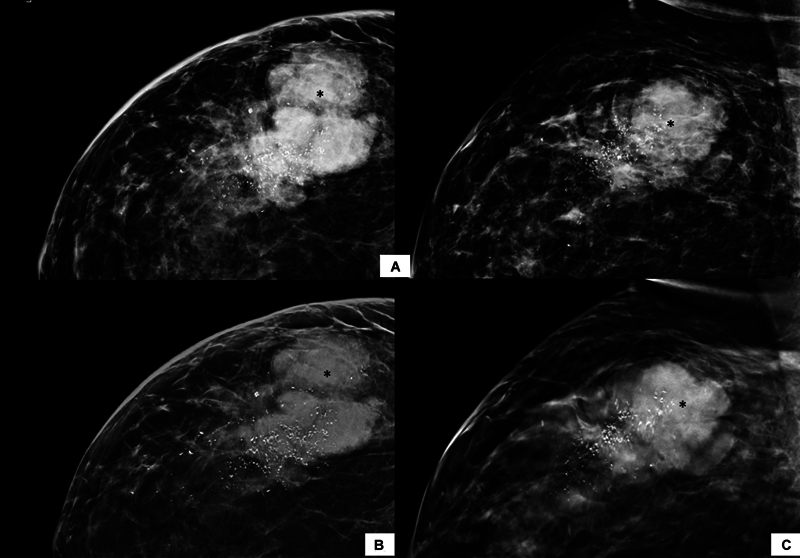

合成乳房x线摄影(SM)是指从数字乳房断层合成(DBT)数据中获得的二维(2D)图像。与传统的全视野数字乳房x线摄影(FFDM)加断层合成相比,它可以减少辐射剂量和扫描时间。目的比较二维FFDM与DBT合成乳房x线照片在诊断人群中的诊断效果。材料与方法经研究所伦理委员会批准,在2年内共获得1468张含FFDM和SM + DBT的乳房x线照片并进行分析。根据2013年美国放射学会乳腺成像报告和数据系统(BI-RADS)词汇,对图像进行报告和比较,包括乳房密度、肿块形态学特征、钙化、不对称或结构扭曲的存在,然后进行BI-RADS分类。采用Kappa值研究两种模式之间的一致性,并记录两组的辐射暴露剂量。结果FFDM和SM + DBT在乳腺密度、肿块特征和钙化检测方面具有很强的一致性(kappa >.8)。SM + DBT对乳腺密度和肿块密度的分期下降无统计学差异。SM组乳头乳晕复合体的可视化较差(50.34% vs. 76.29%),且存在SM特异性伪影,主要与重建算法有关。SM的辐射剂量较高。结论FFDM与SM + DBT诊断效果相当。后者可能对乳房致密的患者特别有用。

Background  Synthesized mammography (SM) refers to two-dimensional (2D) images derived from the digital breast tomosynthesis (DBT) data. It can reduce the radiation dose and scan duration when compared with conventional full-field digital mammography (FFDM) plus tomosynthesis. Purpose  To compare the diagnostic performance of 2D FFDM with synthetic mammograms obtained from DBT in a diagnostic population. Materials and Methods  A total of 1,468 mammograms with both FFDM and SM + DBT images were obtained and analyzed over 2 years, after obtaining approval from the institute ethics committee. The images were reported and compared as per the 2013 American College of Radiology Breast Imaging Reporting and Data System (BI-RADS) lexicon in terms of breast density, morphological features of mass, calcifications, and presence of asymmetry or architectural distortion followed by the BI-RADS category. The agreement between the two modalities was studied using the Kappa value, and the radiation exposure dose was recorded in both groups. Results  FFDM and SM + DBT showed strong agreement for breast density, mass characteristics, and detection of calcifications (kappa > 0.8). Downstaging of breast density and mass density were seen by SM + DBT without any statistically significant difference. The nipple-areola complex visualization was poor in SM (50.34 vs. 76.29% in FFDM), and there were SM-specific artifacts mainly related to the reconstruction algorithm. The radiation dose was higher with SM. Conclusion  FFDM has comparable performance to SM + DBT in diagnostic setup. The latter may be particularly helpful in patients with dense breasts.